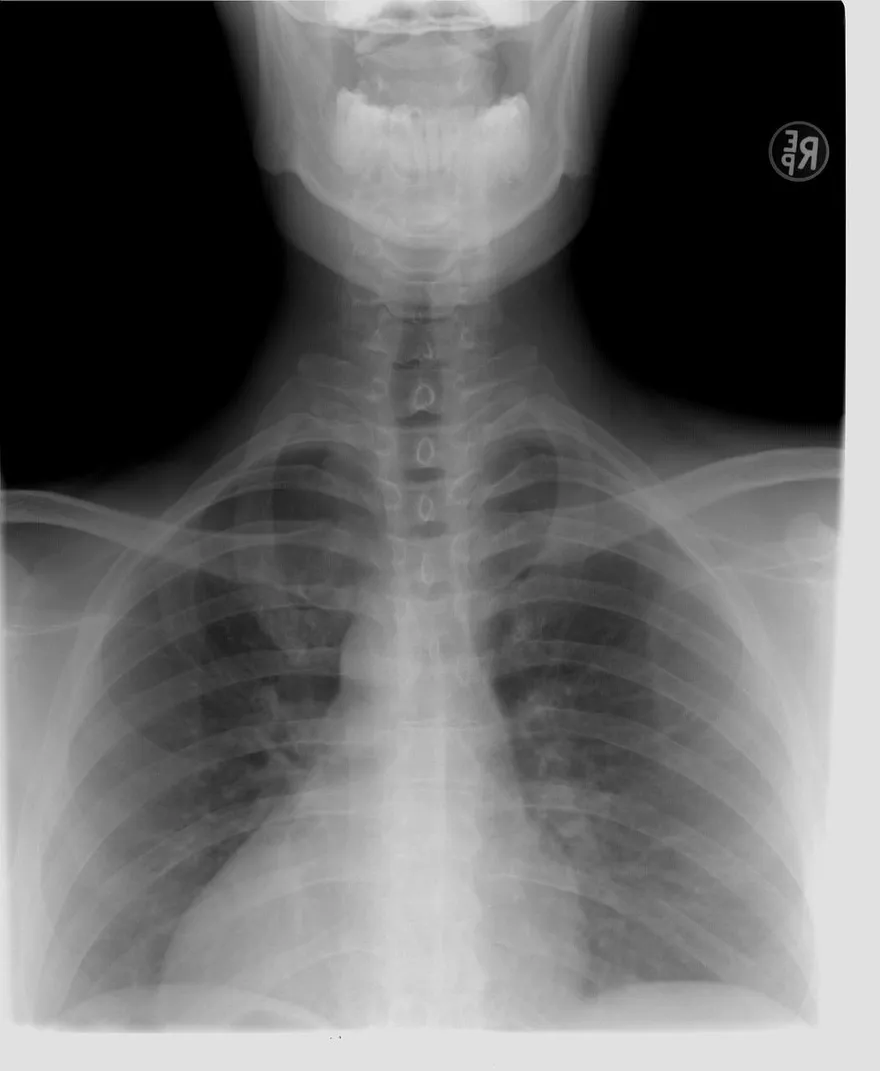

55歲女大腿痛竟是肺癌4期 激動喊:上週X光正常!醫揭原因

X光